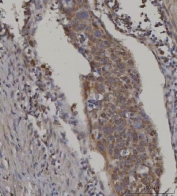

IHC staining of FFPE human esophageal squamous carcinoma tissue with FATP-3 antibody. HIER: boil tissue sections in pH8 EDTA for 20 min and allow to cool before testing.